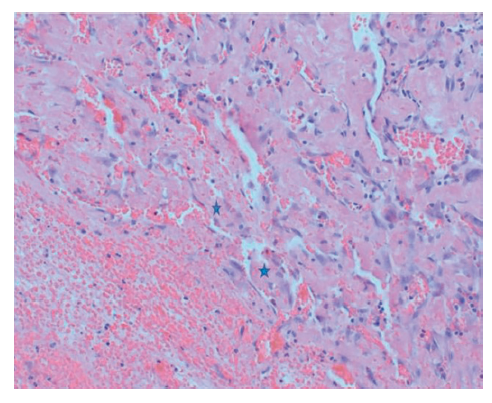

Variations in IPEH histology lend itself to classification into 3 types. The primary form usually arises in the soft tissues of the hand, digits, or head and neck, oftentimes in a dilated vein. Secondary, or “mixed tumors,” arise in the presence of preexisting vascular abnormalities. The third type, extravascular IPEHs, arise in hematomas and are least common. On microscopic examination, these consist of characteristic dilated vascular channels, a fibrous connective tissue core, a monolayer of plump endothelial cells, and papillae. Tumors are generally positive for CD31, CD34, SMA, and factor VIII-related antigen. CD105 is positive on vascular endothelial cells and primary vascular neoplasms, which help differentiate IPEHs from angiosarcomas.6 (Figure 3, Figure 4, Figure 5)